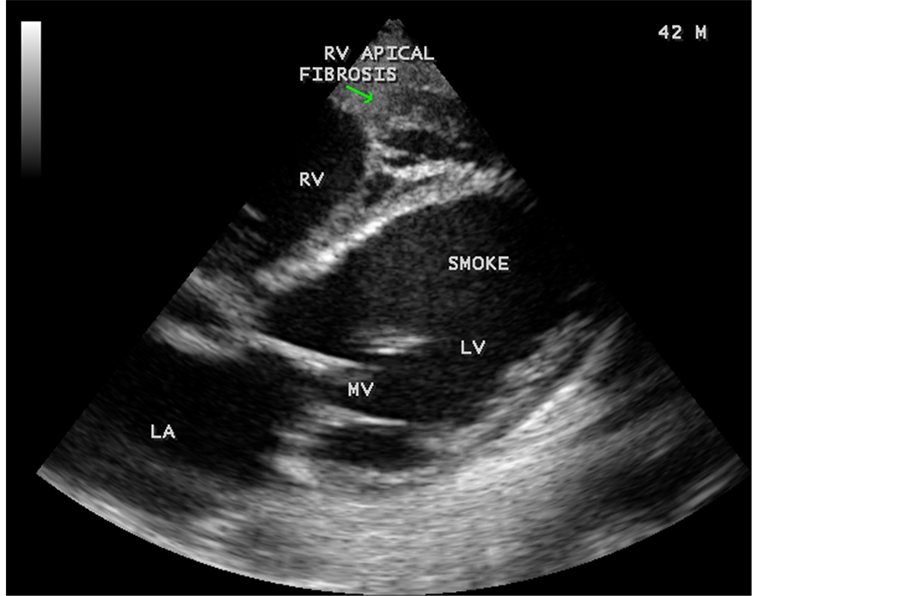

Figure 82. Tilted apical view showing the RV apical fibrosis and smoke (spontaneous echo contrast) in the left ventricle in a 42-year-old male.

RV EMF was detected antenatally in a 22-year-old woman with 8 months amenorrhea as in Figure 67. Endomyocardial fibrosis with left ventricular endocardial calcification and subvalvular fibrosis was detected in a new born with complete AV (atrioventricular) septal defect as shown in Figure 68 to Figure 72. EMF associated with fibrosis of papillary muscle and aneurysmal left ventricle is shown in Figure 74 and Figure 75 in a 56-year-old female. RV EMF associated with right sided pleural effusion, massive ascites and smoke (spontaneous echo contrast) in both ventricles are shown in Figure 76 to Figure 82 in a 42-year-old male. Classical case of RV EMF was shown in Figure 83 and Figure 84 in a 55-year-old male.